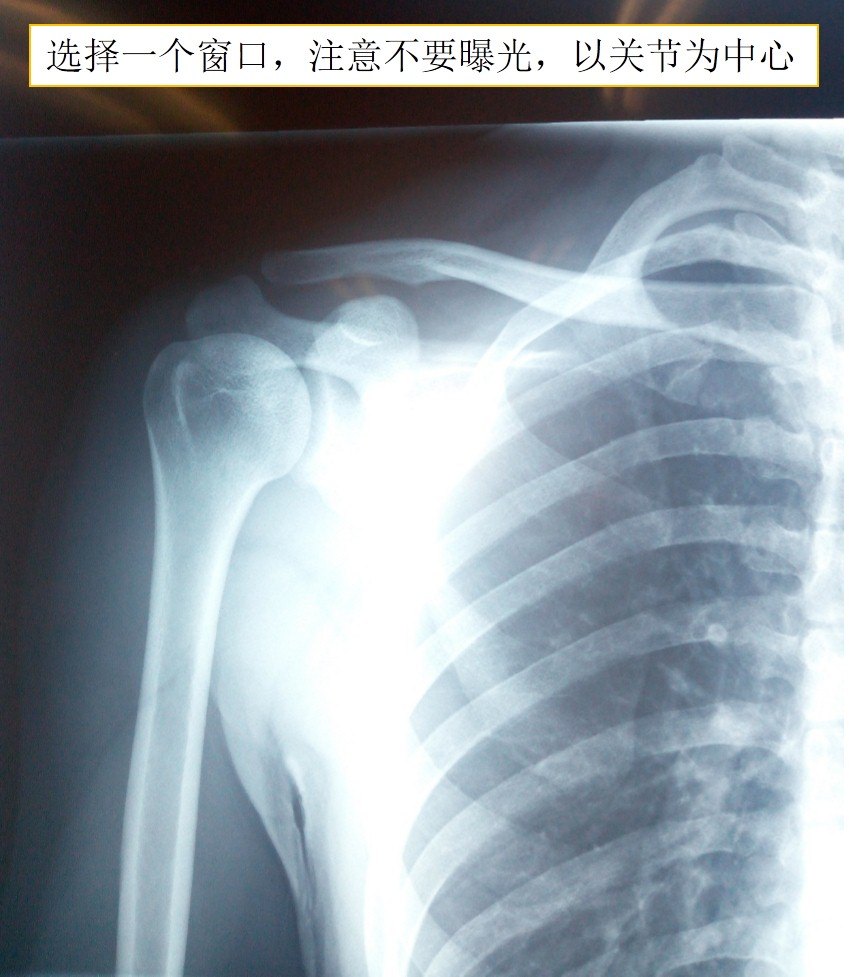

拍片子要:光线好,背景为白色,关闭散光,选择1个最多不超过4个窗口进行拍照。

3.使用玻璃窗户拍照 注意背景要白色,清晰